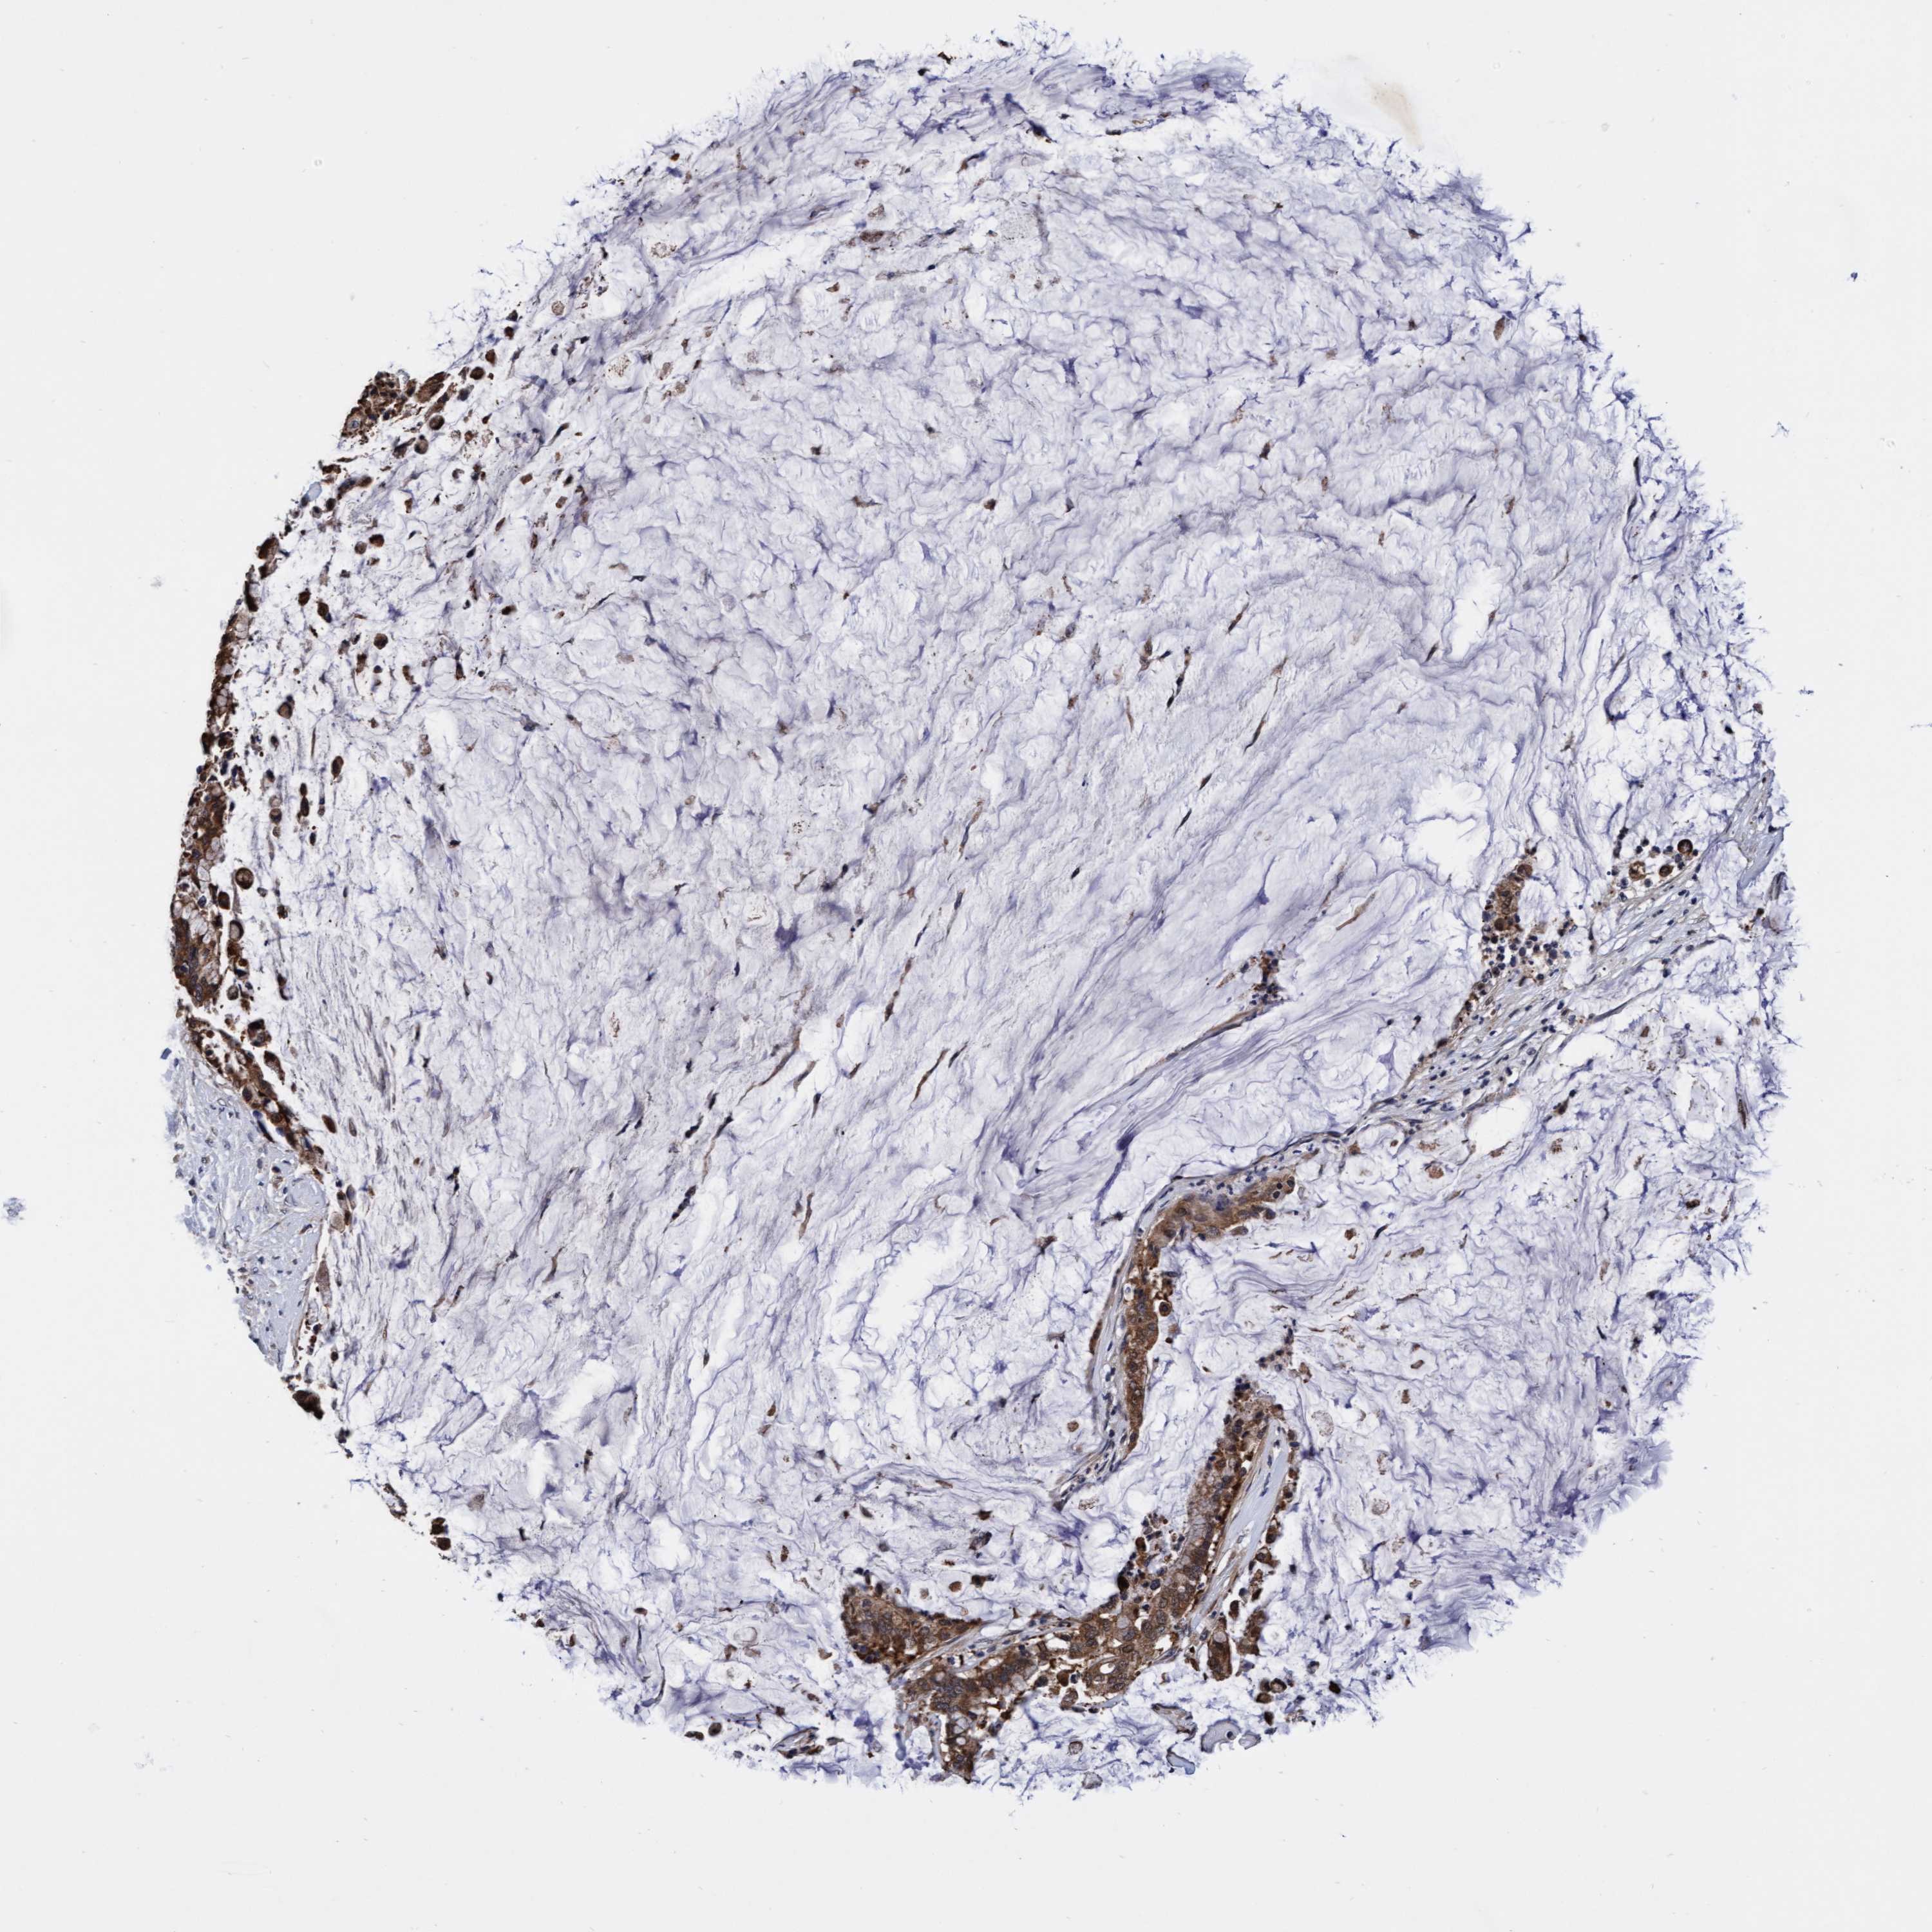

PANCREATIC CANCER - Protein expressioni

A mouse-over function shows sample information and annotation data. Click on an image to view it in a full screen mode. Samples can be filtered based on level of antibody staining by selecting one or several of the following categories: high, medium, low and not detected. The assay and annotation is described here.

Note that samples used for immunohistochemistry by the Human Protein Atlas do not correspond to samples in the TCGA dataset.

Antibody stainingi

Antibody staining in the annotated cell types in the current human tissue is reported as not detected, low, medium, or high, based on conventional immunohistochemistry profiling in selected tissues. This score is based on the combination of the staining intensity and fraction of stained cells.

Each image is clickable and will lead to virtual microscopy that enables deeper exploration of all samples and also displays staining intensity scores, fraction scores and subcellular localization as well as patient and tissue information for each sample.

Antibody HPA021633

Antibody HPA023249

Antibody HPA026561

Antibody CAB002501

Adenocarcinoma, NOS

Adenocarcinoma, metastatic, NOS